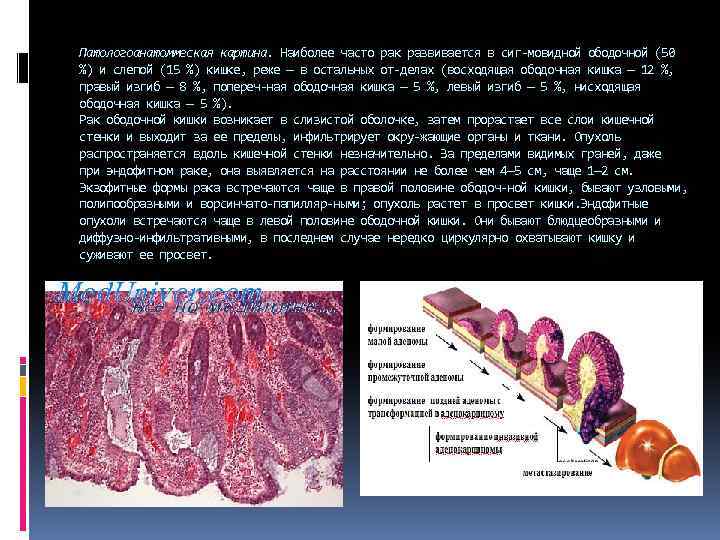

Патологоанатоммеская картина. Наиболее часто рак развивается в сиг мовидной ободочной (50 %) и слепой (15 %) кишке, реже — в остальных от делах (восходящая ободочная кишка — 12 %, правый изгиб — 8 %, попереч ная ободочная кишка — 5 %, левый изгиб — 5 %, нисходящая ободочная кишка — 5 %). Рак ободочной кишки возникает в слизистой оболочке, затем прорастает все слои кишечной стенки и выходит за ее пределы, инфильтрирует окру жающие органы и ткани. Опухоль распространяется вдоль кишечной стенки незначительно. За пределами видимых граней, даже при эндофитном раке, она выявляется на расстоянии не более чем 4— 5 см, чаще 1— 2 см. Экзофитные формы рака встречаются чаще в правой половине ободоч ной кишки, бывают узловыми, полипообразными и ворсинчато папилляр ными; опухоль растет в просвет кишки. Эндофитные опухоли встречаются чаще в левой половине ободочной кишки. Они бывают блюдцеобразными и диффузно инфильтративными, в последнем случае нередко циркулярно охватывают кишку и суживают ее просвет.

Большинство злокачественных опухолей ободочной кишки имеет строе ние аденокарциномы (примерно у 90 % больных), реже — слизистой адено карциномы (слизистого рака), перстневидно клеточного рака (мукоцеллю лярного рака), плоско клеточного (ороговевающего и неороговевающего) и недифференцированного рака. Специфической особенностью рака ободочной кишки является довольно длительное местное распространение опухоли (включая прорастание в ок ружающие органы и ткани) при отсутствии метастазирования в регионар ные лимфатические узлы, которое может появиться довольно поздно. Метастазирование происходит лимфогенным (30 %), гематогенным (50 %) и имплантационным (20 %) путем. Метастазы чаще всего возникают в печени, реже — в легких, костях, поджелудочной железе.